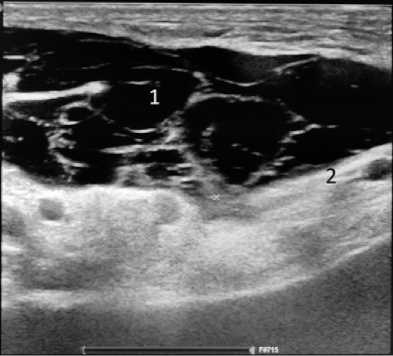

Обследование 242 пациентов показало, что диагностика паховой грыжи у мужчин не сложна. Клинические проявления заболевания позволяли во время осмотра установить диагноз, а при УЗИ оценить состояние тканей в паховых областях, локализацию грыжи (прямая или косая) и определить содержимое грыжевого мешка, что имело значение для установления сроков выполнения операции. У женщин были проблемы ранней диагностики неосложнённой грыжи при астеническом телосложении и у гиперстеников, страдающих ожирением. На ранних сроках развития грыжи женщины предъявляли жалобы на боли в паху при отсутствии над ним опухолевидного образования. При этом из-за особенностей расположения наружного отверстия пахового канала в проекции половых губ определить грыжу при пальцевом исследовании было не всегда возможно. Объяснить эту особенность можно тем, что при косой паховой грыже, спускающейся через глубокое паховое кольцо, грыжевой мешок расслаивает круглую связку матки, имеющей малый диаметр, не выходит за её размеры. При прямой паховой грыже грыжевой мешок смещается параллельно круглой связке матки, подходит к наружному паховому кольцу и располагается под ним в виде опухолевидного образования, что позволяет клинически поставить диагноз. У пациенток с ожирением из-за избытка жировой ткани в надлобковой области определить грыжевой мешок при отсутствии клиники ущемления, выходящий из наружного отверстия пахового канала, практически очень сложно, что для установления диагноза требует применения инструментальных методов исследования. Применение УЗИ позволяло установить и подтвердить диагноз у пациентов с паховой грыжей. На рисунках 1 и 2 представлены результаты УЗИ у пациента Н., 37 лет, с двухсторонней паховой грыжей, которые позволили подтвердить диагноз и выполнить операции по поводу паховых грыж открытым способом с двух сторон. На рисунке 3 представлены результаты УЗИ пациентки Н., 45 лет; диагноз – правосторонняя косая паховая грыжа: вид грыжевого мешка, расположенного в круглой связке матке.

Рисунок 1. Пациент Н, 54 года. Изображение левосторонней косой паховой грыжи при ультрасонографическом исследовании: 1 – подкожно-жировая клетчатка; 2 – наружная косая мышца живота; 3 – грыжевой мешок; 4 – поперечная мышца живота и апоневроз, прилегающие к глубокому паховому кольцу

Figure 1. Patient H., 54 years old. Ultrasonographic image of a leftsided indirect inguinal hernia: 1 – subcutaneous fat; 2 – external oblique abdominal muscle; 3 – hernial sac; 4 – transverse abdominal muscle and aponeurosis adjacent to the deep inguinal ring